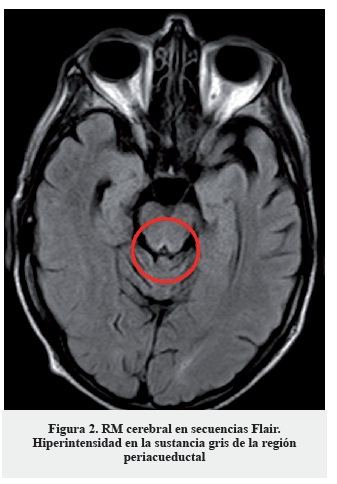

La clínica, los hallazgos en la exploración neurológica y el antecedente de cirugía resectiva gastrointestinal hacen sospechar como primera posibilidad diagnóstica una encefalopatía de Wernicke, probablemente desencadenada en el contexto de vómitos y administración de suero glucosado. Dada la alta morbimortalidad del cuadro se inició de forma urgente tratamiento sustitutivo con tiamina (vitamina B1) 300 mg intramuscular, asociada a cianocobalamina (vitamina B12) y piridoxina (vitamina B6) parenterales. No se pudo realizar determinación de niveles séricos de vitamina B1 previa a la administración del tratamiento de reposición. El tratamiento se instauró de forma diaria durante diez días, objetivando una mejoría sintomática a las veinticuatro horas tras la primera dosis, progresiva. Como única prueba complementaria se solicitó un estudio de neuroimagen con RM cerebral (secuencias habituales, difusión y secuencias dinámicas tras la administración de contraste intravenoso (gadolinio)) en la que se apreció hiperseñal simétrica en secuencias T2 y Flair de la porción medial de ambos tálamos (Figura 1), cuerpos mamilares y sustancia gris periacueductal (Figura 2), que se acompaña de una restricción de la difusión en la porción medial de ambos tálamos (Figura 3); además se evidenció hiposeñal simétrica y bilateral de ambos núcleos pálidos; todo ello compatible con encefalopatía de Wernicke.

Se señalan en las imágenes dichos hallazgos. Los hallazgos de resonancia magnética, si bien son poco sensibles (53%), son altamente específicos (93%), e incluso se señalan como patognomónicos en algunos manuales/artículos publicados, por lo que el diagnóstico diferencial no se establece con base en estos hallazgos. No es posible recoger imágenes de mayor resolución, pues estas han sido obtenidas directamente del programa utilizado por los radiólogos del hospital.